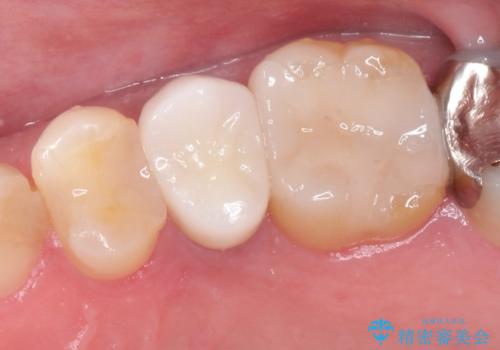

- 左上の後ろから3番目の歯のかぶせ物が適合不良であったので、根管治療を行い、オールセラミックを装着する計画としました。

またその隣の目立つ銀歯も同時に、セラミックに交換することとしました。

根管治療からかぶせ物まで精度の高い治療をおこないました。